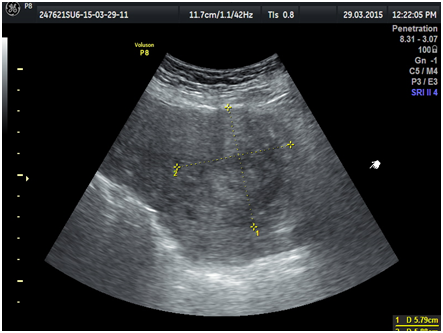

A 29-year-old multiparous woman at 11weeks’ gestation was referred to our hospital for termination of pregnancy due to suspected placenta accreta or cesarean scar ectopic by abnormal vasculature around lower uterine segment gestational sac on ultrasound. She had delivered 2male children by cesarean section. The patient underwent ultrasound due to complain of vaginal bleeding. It revealed lower uterine segment pregnancy with abnormal vasculature in the placenta bed suspicious of placenta accreta or cesarean scar ectopic pregnancy about 10weeks gestation (Figure 1). The decision was done to evacuate the pregnancy vaginally by surgical means. The patient underwent surgical evacuation under ultrasound guidance but severe vaginal bleeding occurred. The procedure was ended and uterovaginal packing was done for 24hrs. The patient was vitally stable. The procedure was performed transabdominal ultrasound examination after 24hrs that revealed bulky uterus with hematoma inside cavity and there was a defect (3cm×2.0cm) in the lower anterior uterine wall with no fluid collection in the abdomen (Figures 2-5). The patient was vitally stable with no vaginal bleeding. We removed the vaginal pack intraoperative under general anesthesia, prepared for laparotomy in case of severe bleeding. No bleeding occurred, the patient discharged after 1 week and follow-up after one month revealed normal uterus.

Figure 4Uterine defect about 3cm.

Figure 5Hematoma intrauterine about 5cm.